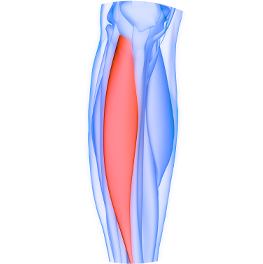

筋肉の厚さ

筋膜構造